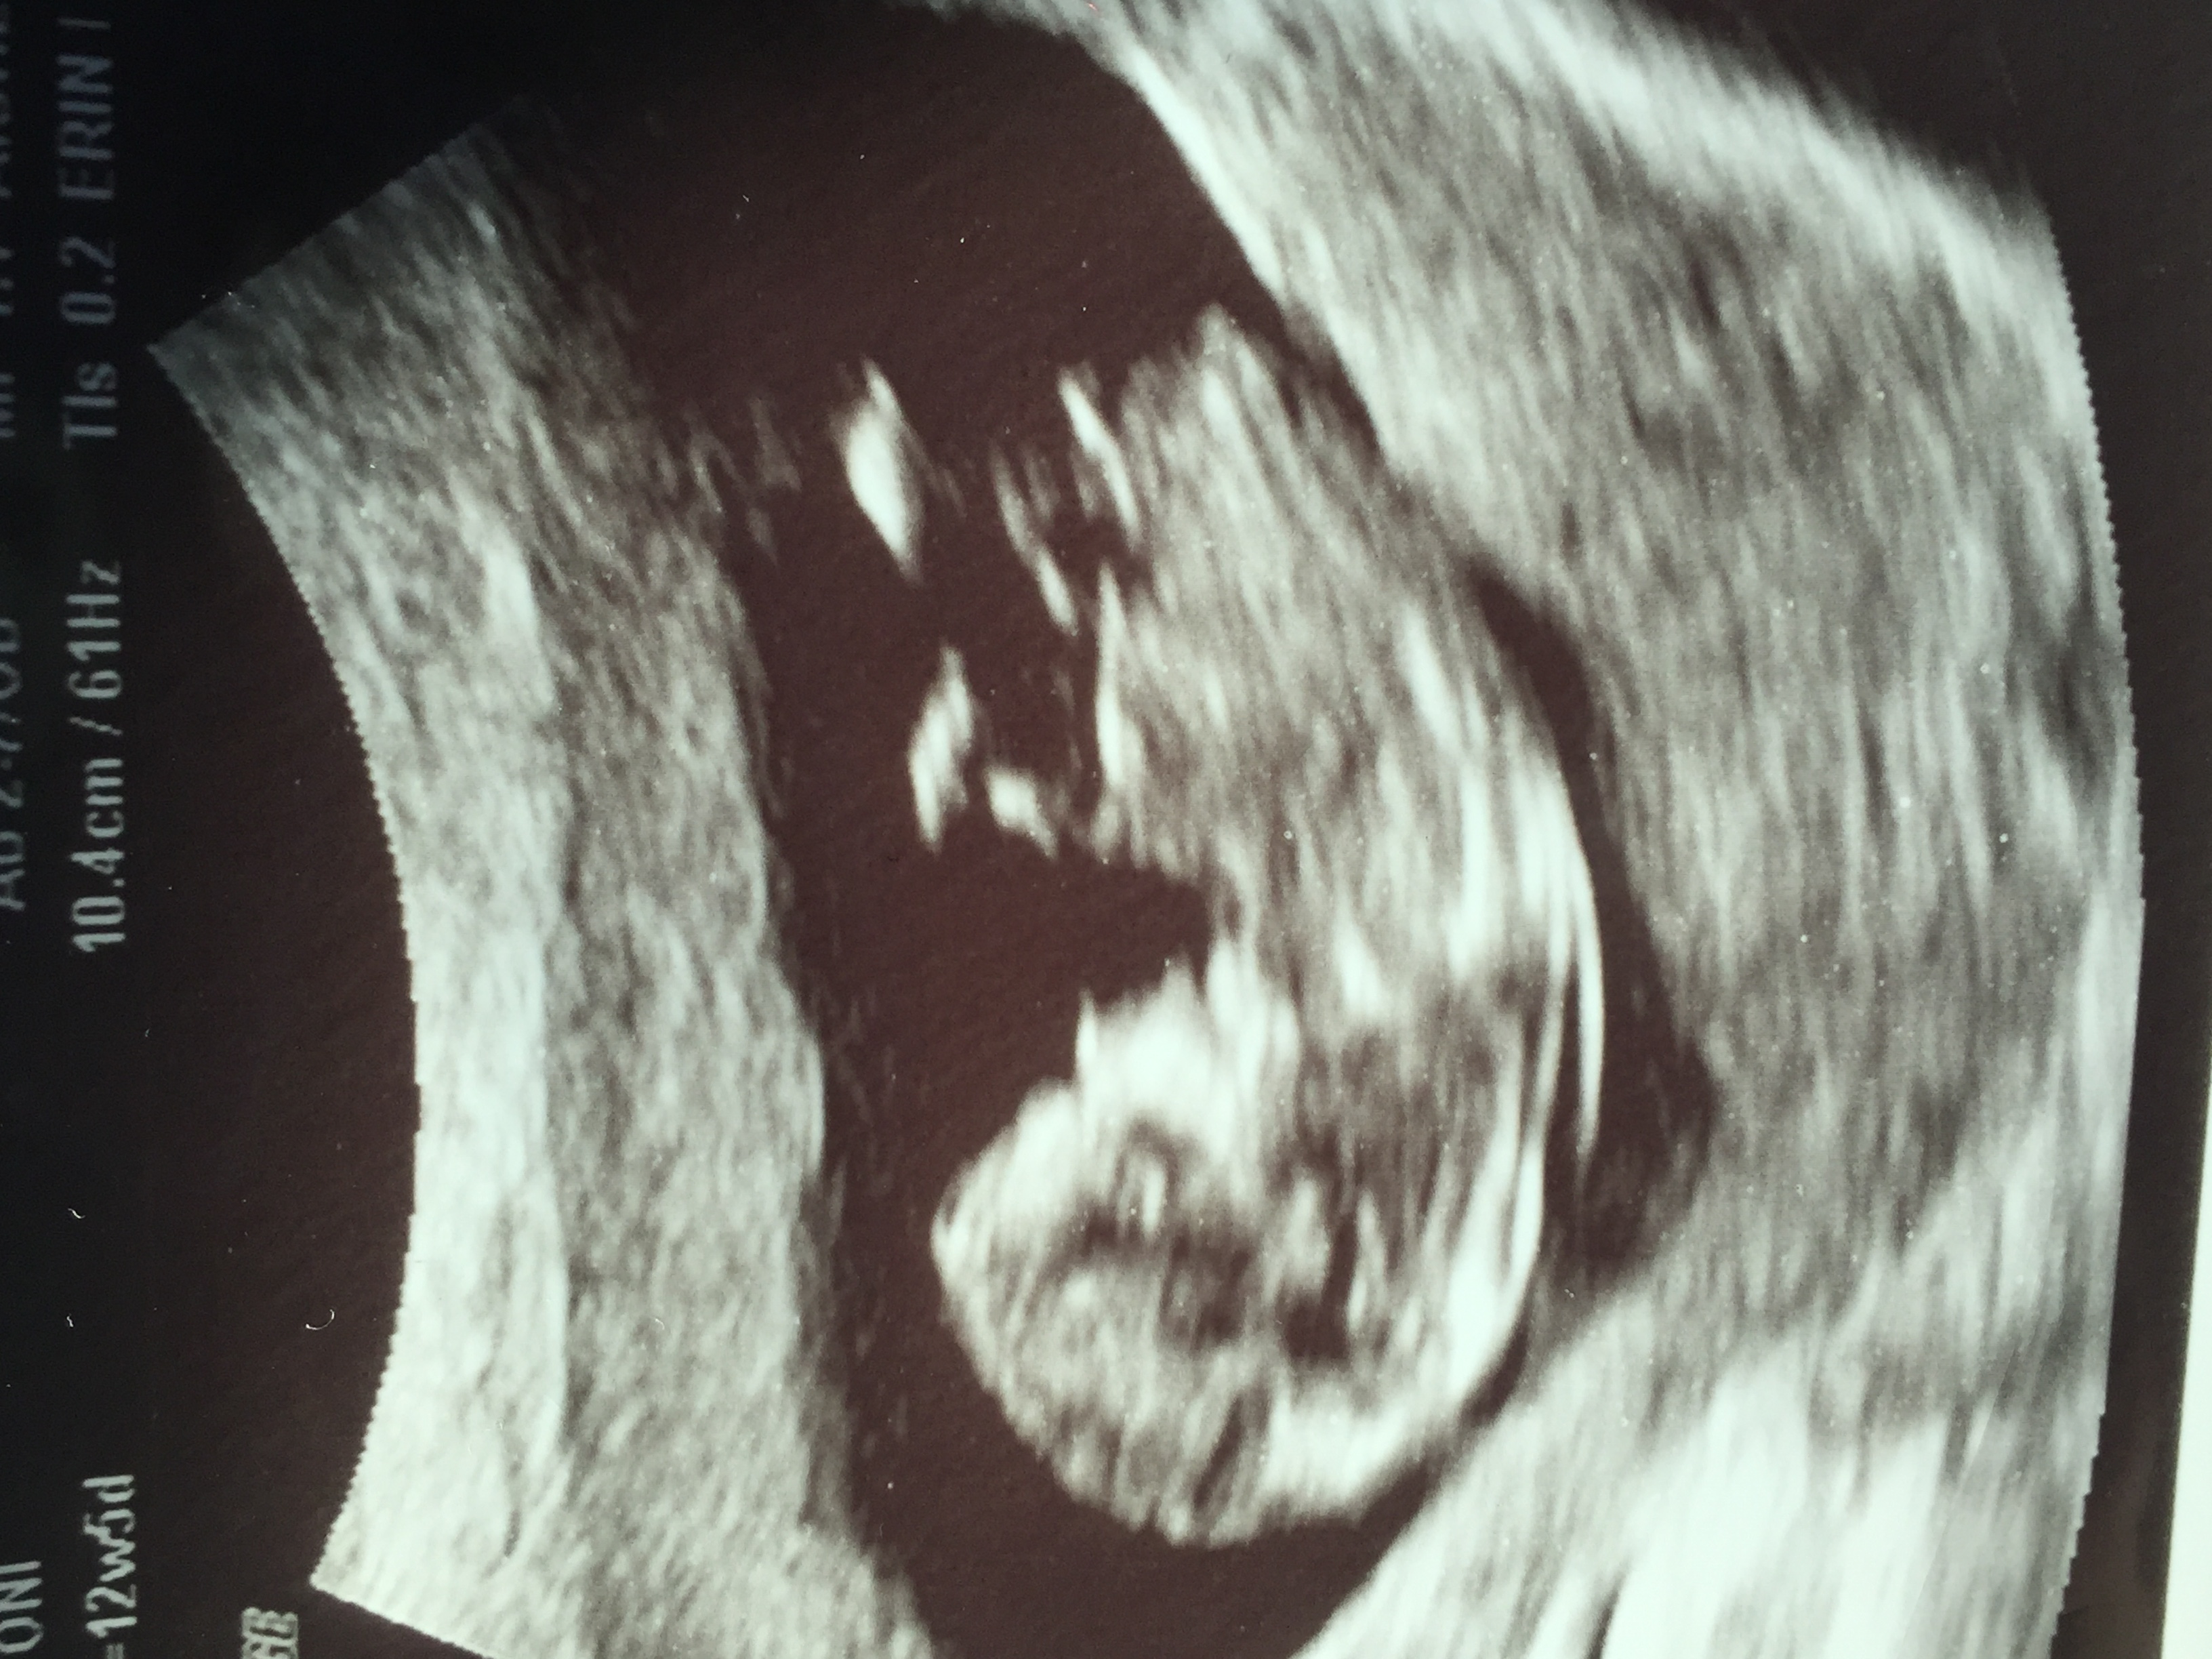

12-5 nub guesses please! 😊